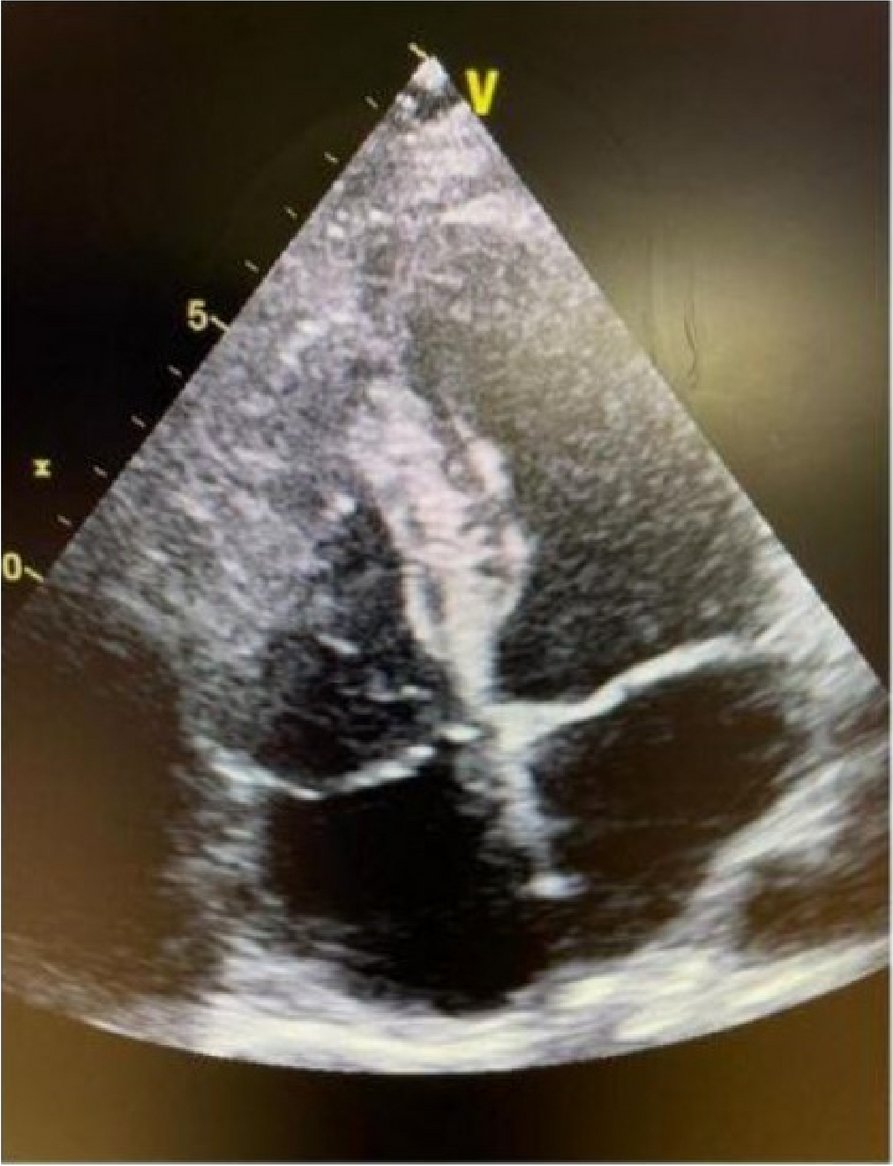

A few hours after the admission in ICU he reported a blunt abdominal pain, mainly on the right side, nausea and the exams showed increased amylase levels, urologists excluded any surgical involvement of pancreatic tissue and suspected a transient sphincter of Oddi dysfunction [3]. After one night in ICU he was transferred to the urology ward due to his clinical stability, even though Amylase peaked at 2340 U/l. Two days later abdominal pain increased to severe, with characteristics of peritonism and increased inflammatory markers. An abdomen-thorax CT scan revealed acute pancreatitis (AP) (Figure 1) and he was transferred to ICU. He started a standard treatment for acute pancreatitis and antibiotic therapy [4].

Fig. 1 (abstract A21).

See text for description